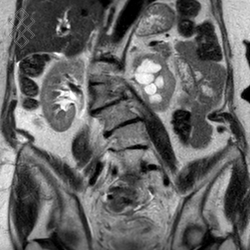

IRM des Reins / Artères rénales